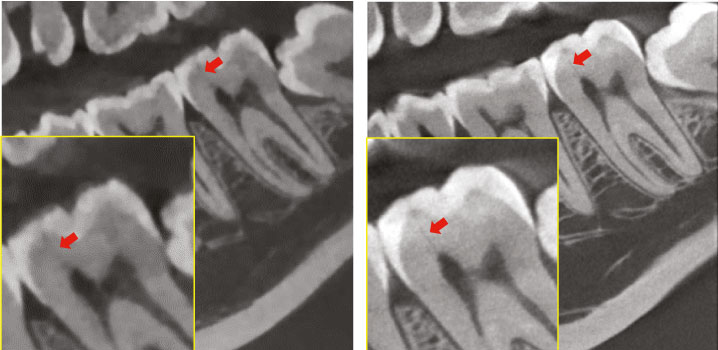

Низкая доза облучения и высокое разрешение

Объем сканирования 4x4 см и размер вокселя 49,5 микрон в режиме Endo позволяет получить изображения высокой четкости. Данный режим идеально подходит для эндодонтического использования, позволяя стоматологу исследовать необходимую зону интереса при максимальном разрешении.

• вкладка Endo с новыми инструментами для планирования лечения каналов зубов:

измерения кривизны каналов, вычисления поперечного сечения, визуализации каналов,

сегментирования зубов для лучшего понимания анатомического и функционального строения

зуба.

• вкладка Endo с новыми инструментами для планирования лечения каналов зубов: измерения кривизны каналов, вычисления поперечного сечения, визуализации каналов, сегментирования зубов для лучшего понимания анатомического и функционального строения зуба.